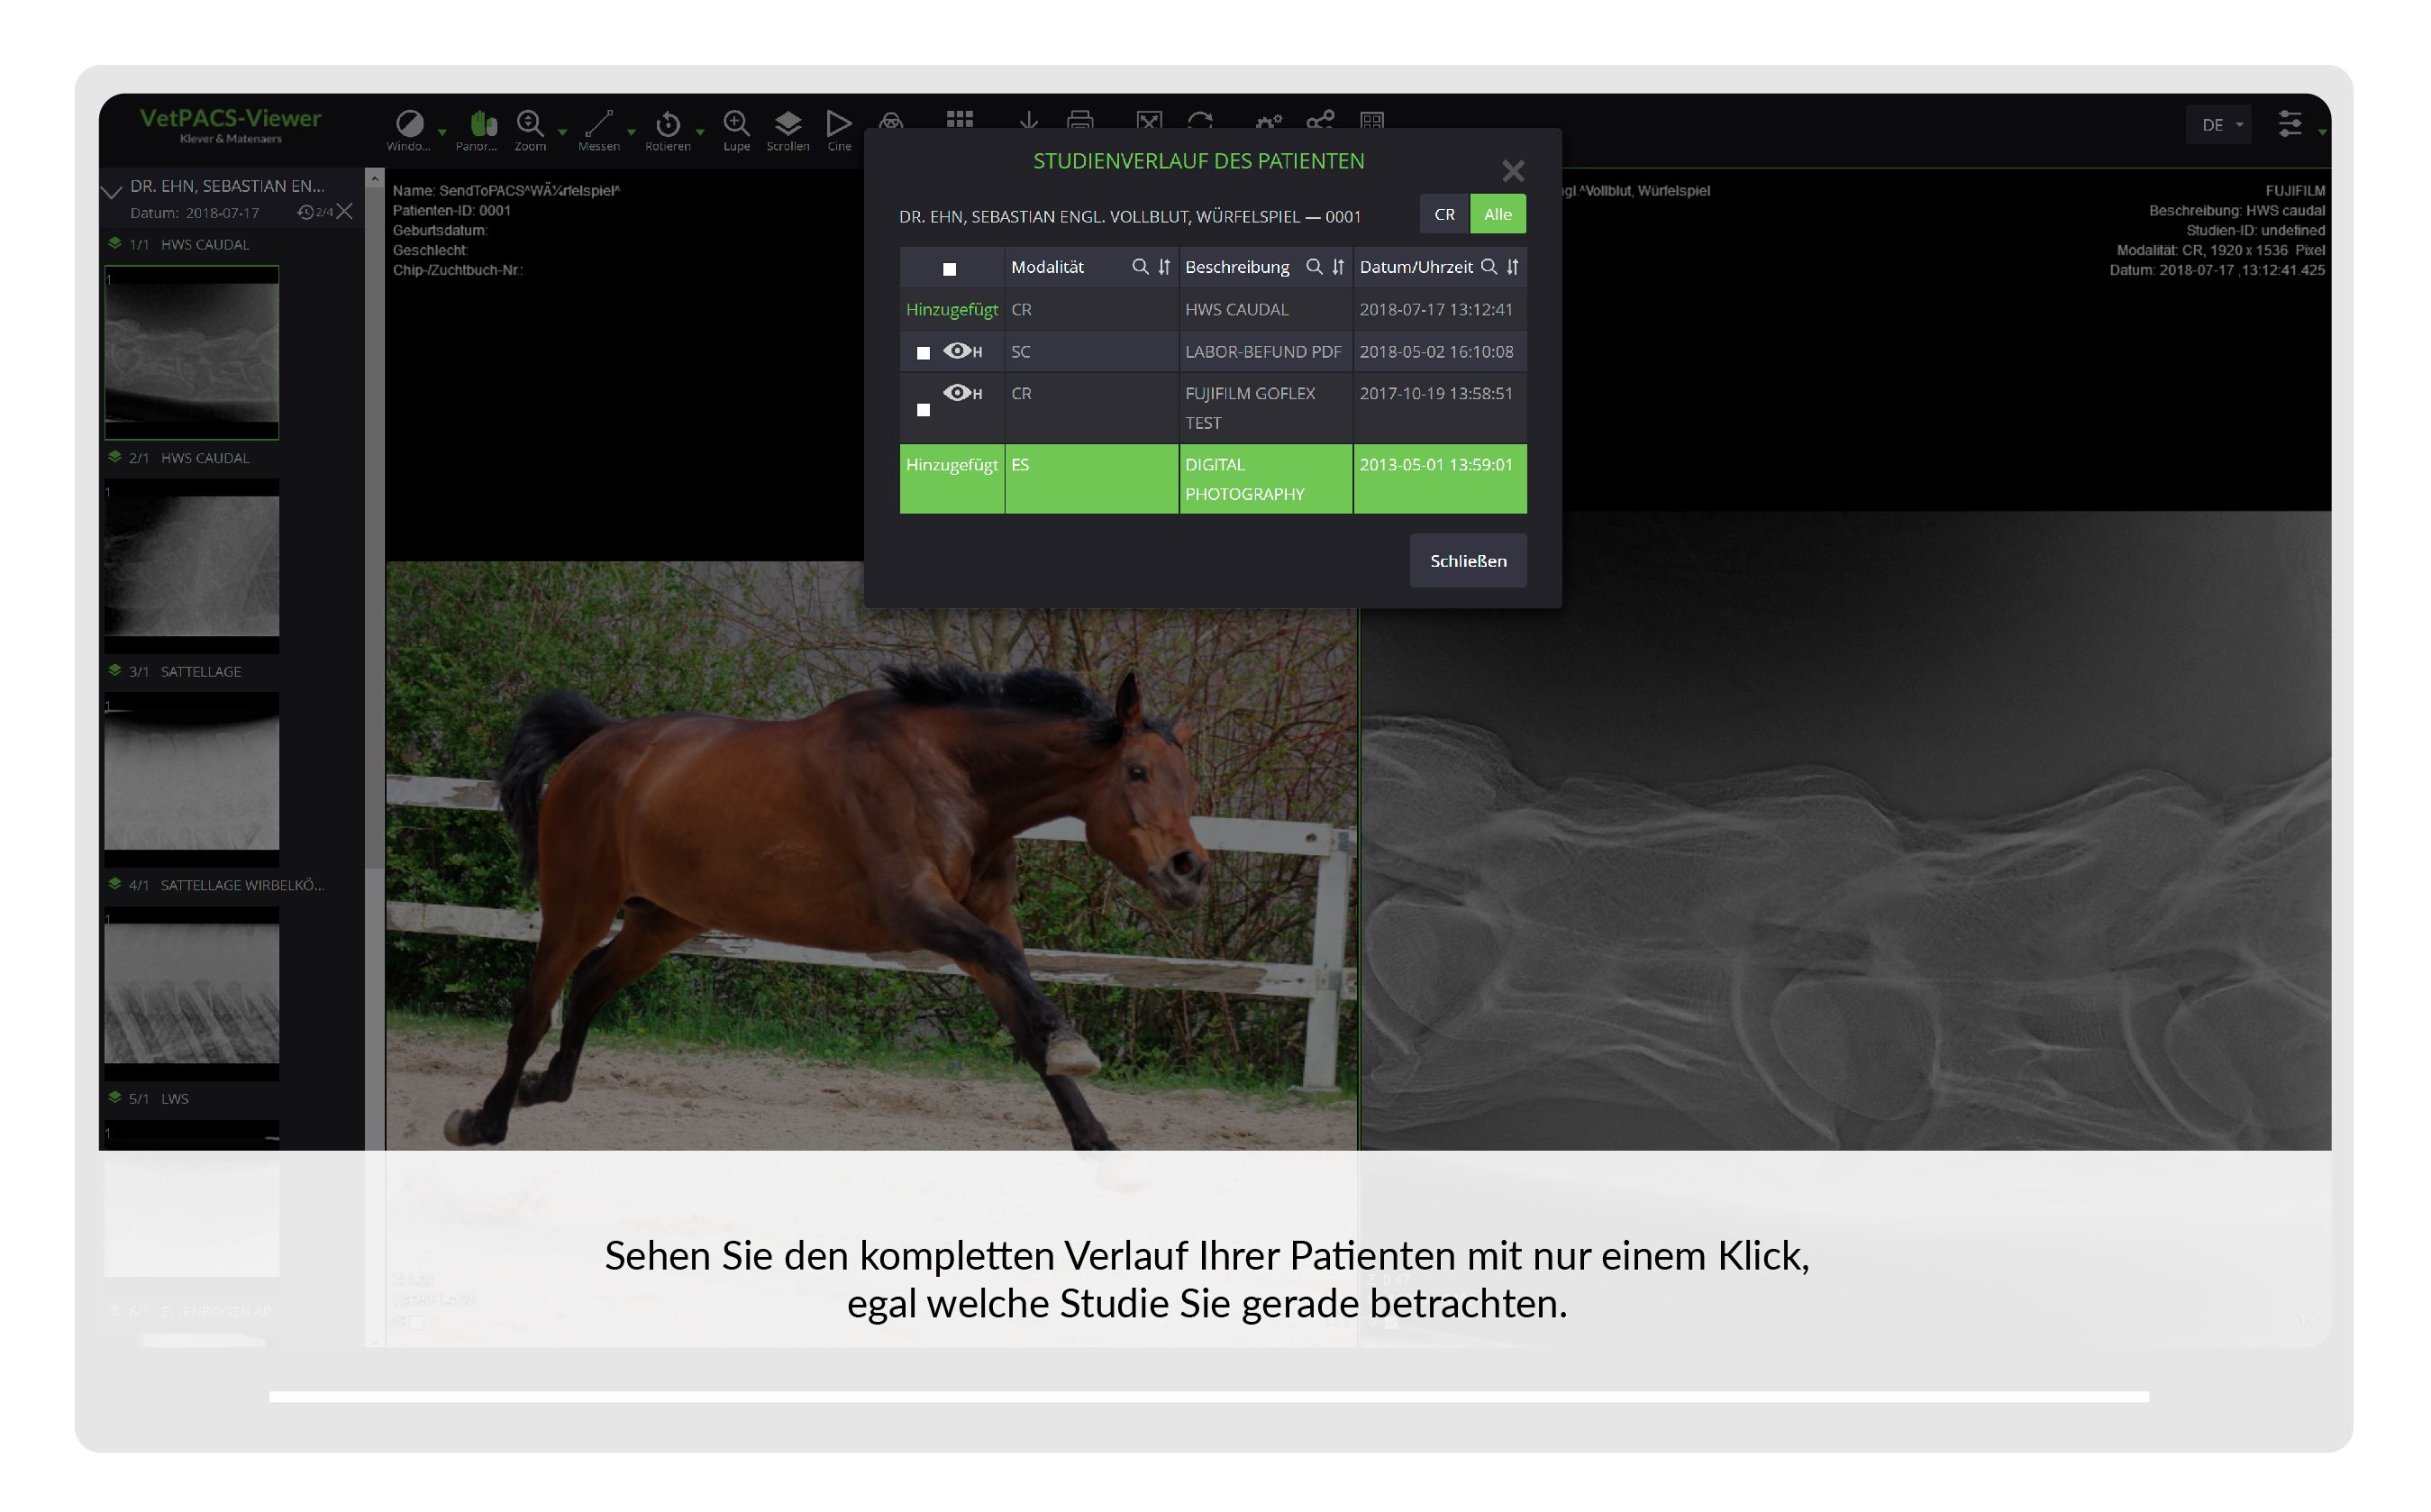

VetPACS

Unsere Lösung zur sicheren Archivierung, Befundung und Kommunikation von medizinischen Bildern und Daten.

| ✓ | Alle Funktionen sind auf veterinär-spezifische Anforderungen optimiert. |

| ✓ | Der integrierte DICOM-Viewer dient zur Betrachtung aller im VetPACS archivierten Daten. |